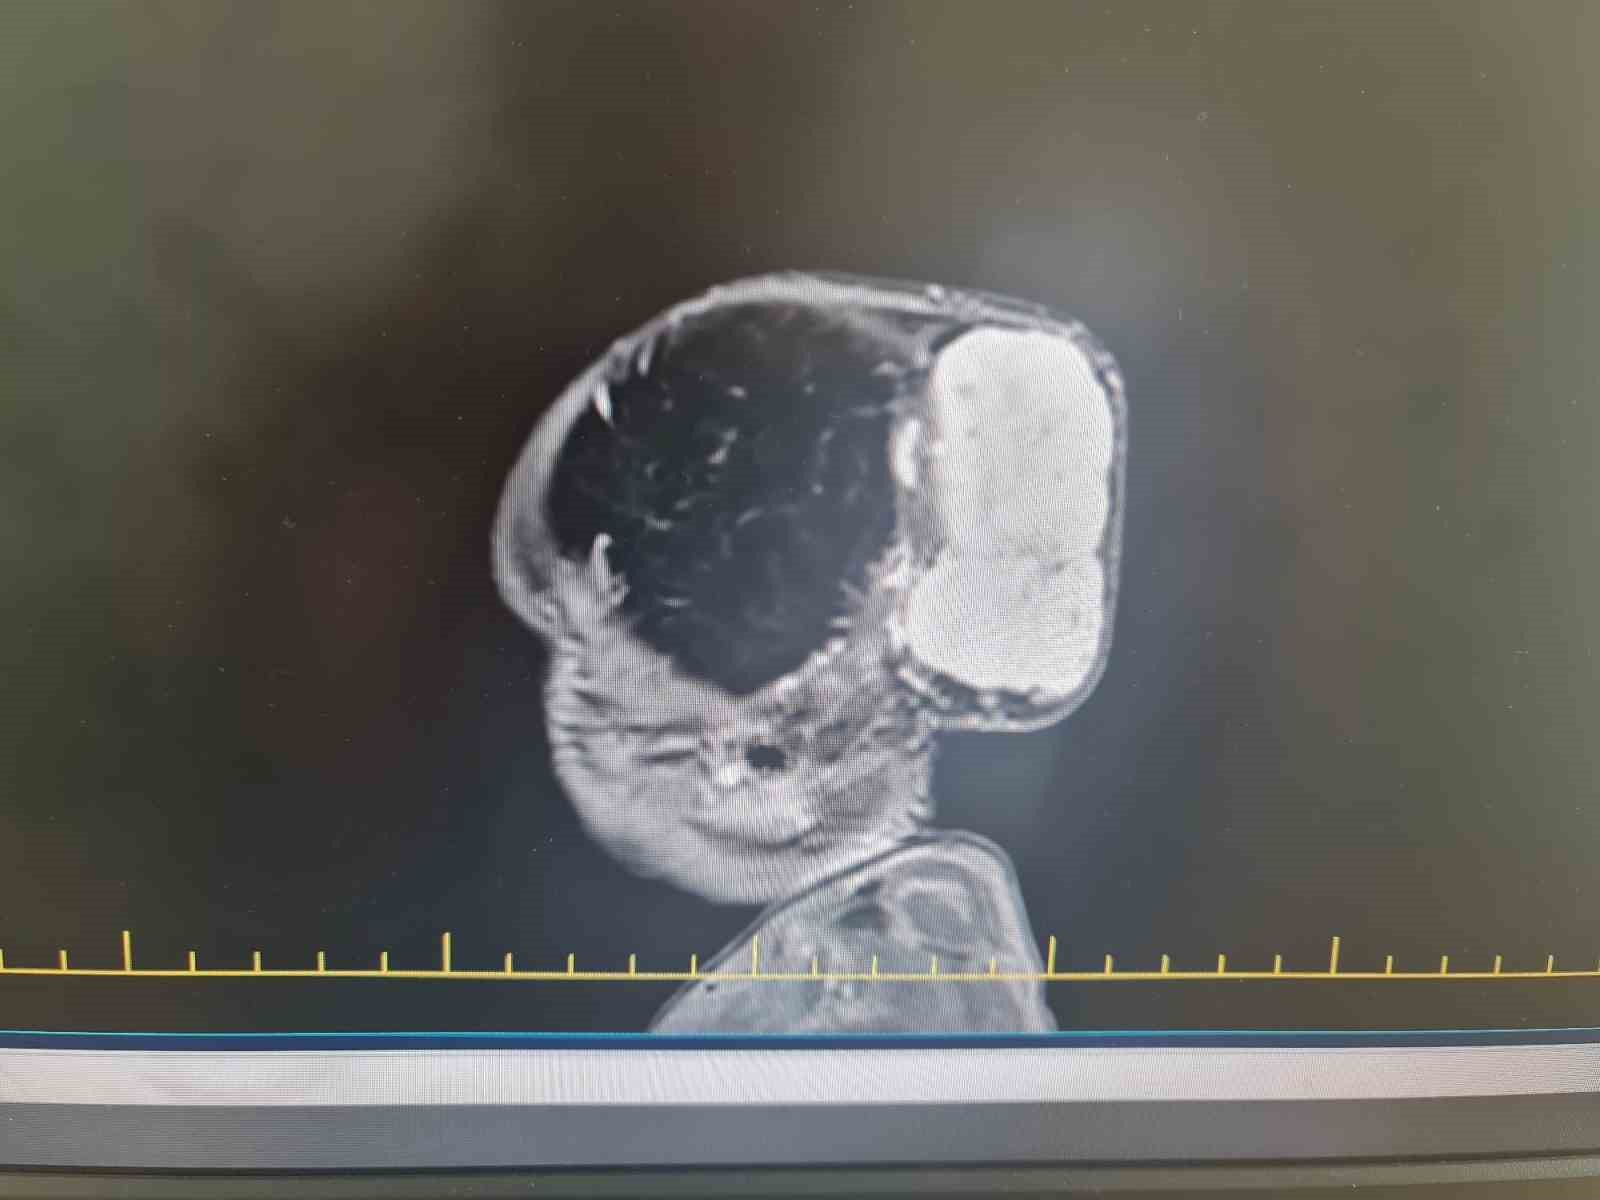

Gaziantep’te Yalçın Enes ve Tuğba Yalçın çiftinin 1,5 yaşındaki çocukları Talha, Gaziantep Şehir Hastanesinde kafasında büyük bir kitle ile dünyaya geldi. Aynı hastanede yapılan tetkiklerde minik Talha’nın kafatasında 7 x 6,5 x 4 santimetre boyutlarında, dünyada nadir görülen vakalar arasında yer alan bir tümör tespit edildi.

Op. Dr. Ali Yayla, "Hastamız Talha bebek, başında dev bir kitle ile doğdu. Yaptığımız tetkikler ve görüntüleme sırasında tümörün hızla büyüdüğünü ve kafa tası kemiklerini harap ettiğini, beyne de baskı yaptığını gördük. Bunun üzerine ameliyat planladık. Fakat bu tümörün özelliğinden dolayı çok fazla damar yapısı vardı. Kanlanması çok fazlaydı ve tümörün kanama riski nedeniyle hayati tehlikesi bu cerrahi işlemle yüksek düzeydeydi. Bu nedenle cerrahi stratejimizi tekrar ve yeniden kurduk. Buna göre basamaklandırılmış ve multidispliner bir yaklaşım sunduk. Öncesinde girişimsel radyoloji ekibi hastaya bir embolizasyon işlemi yaptı ve tümörün kanlanmasını azalttı. Hemen bir gün sonra plastik cerrahisi ve beyin cerrahisinden oluşan bir ekiple, yaklaşık 4 saat süren bir ameliyatla tümörün tamamını başarılı bir şekilde çıkardık. Hastamız bundan herhangi bir zarar görmedi ve sağlığı da gayet iyi seyrediyor. Çocuğumuzu ailesine sağ salim teslim ettik. Tabii bu işlemin arka planında çalışan yeni doğan çocuk yoğun bakım, çocuk hematolojisi, beyin cerrahisi, plastik cerrahi, anestezi olmak üzere büyük bir ekip var. Doktorundan hemşiresine ve sağlık personeline, bütün hastane yönetimine bir buçuk ay boyunca gayret gösterildi ve sonunda da çocuğumuz sağ salim bir şekilde ailesine teslim edildi" dedi.

Bu tarz tümörlerin nadir olarak görüldüğünü aktaran Op. Dr. Ali Yayla, bebeğin taburcu olmasında herhangi bir sorun olmadığını söyleyerek, "Tümörün boyutları yaklaşık 7 x 6,5 x 4 santimetre çaplarındaydı. Bu büyüklükte bir tümör dünyada nadir bir şekilde bu yaş grubunda görülebiliyor. Bu operasyonu başarılı bir şekilde Gaziantep Şehir Hastanesi’nde uygulamak da bizim için büyük bir gurur oldu. Taburcu olmasında herhangi bir sorun yok bugün dördüncü günü. Ama biraz daha bekleyip güvende olmasını istiyoruz. Dolayısıyla dördüncü gün tamamladık, beşinci gün taburcu olabilir" ifadelerini kullandı.